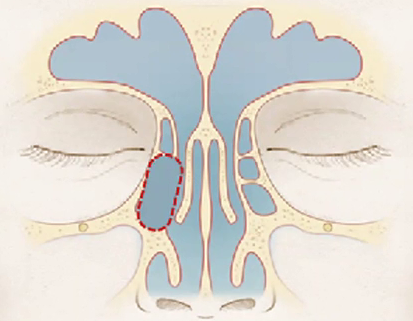

Cite os limites do recesso do seio frontal:

• Anterior = Frontal beak (e Agger Nasi).

• Posterior = Bula etmoidal

• Medial = Porção vertical da concha média

• Lateral = Lâmina Papirácea